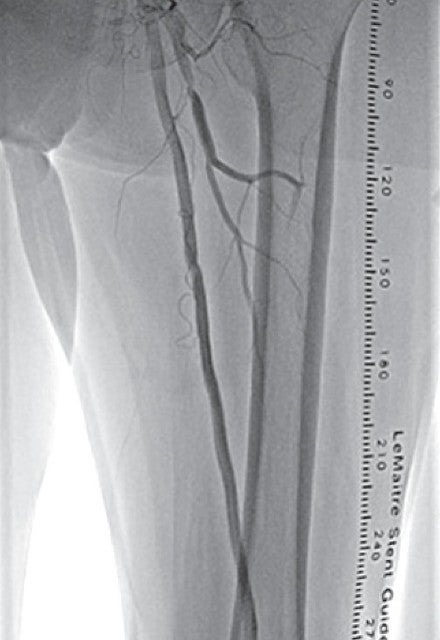

右大腿動脈穿刺、0.035 inchワイヤーを用いて、ガイディングシース 6 Fr 60 cmを左外腸骨動脈まで誘導し、造影を行った(図1.2)。体表面エコーガイドのもと、マイクロカテーテルと0.014 inch フロッピー300 cmワイヤーで、確実に浅大腿動脈入口部から血管真腔内を進めた。0.014 inch フロッピー300 cmワイヤーを抜去し、血管狭窄部貫通用カテーテルに交換し、閉塞部位を慎重に進め、貫通に成功した。血管狭窄部貫通用カテーテルにエクステンションワイヤーをつなげ、マイクロカテーテルを抜去、0.018 inchの径 2.0/長 20 mmバルーンで閉塞部位を拡張した。マイクロカテーテルを末梢まで進め、血管狭窄部貫通用カテーテルを抜去、0.014 inch 300 cm ワイヤーに交換、血管内超音波で病変部の観察を行った。ほぼ真腔を捉えていることが確認できたため、径 4.0/長 250 mmバルーンで閉塞全域を拡張した。一部石灰化病変により、拡張不良部位を認めたため(図3)、径 3.0/長 40 mm ノンコンプライアントバルーンで追加拡張を行った。再度、径 4.0/長 250 mmバルーンで閉塞全域を拡張した(図4)。血管内超音波で閉塞領域を観察し、ほぼ真腔を捉えていることが確認できた。ついで、径 5.0/長 250 mmバイアバーン® ステントグラフトを留置し、グラフト内をバルーンで後拡張した。血管内超音波でグラフト拡張および浅大腿動脈入口部を確認した(図5.6)。結果、左浅大腿動脈の良好な血流を得た(図7)。